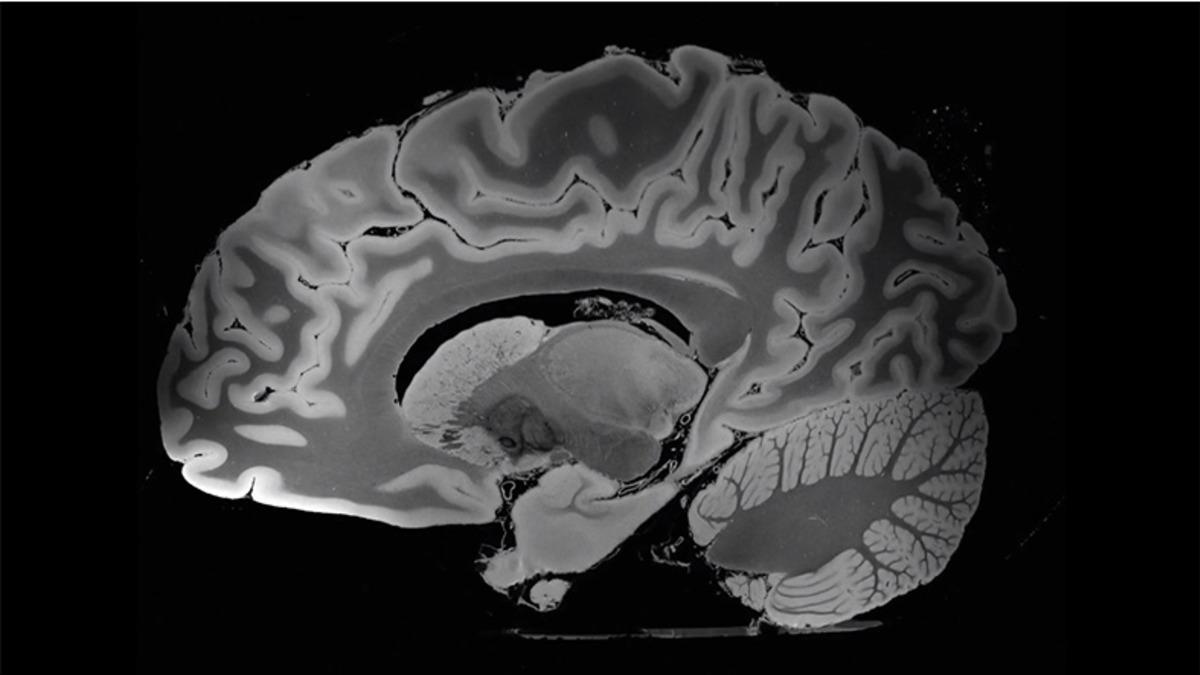

100 saatten fazla süren bir MR taraması, tüm insan beyninin daha önce eşi benzeri görülmemiş derecede ayrıntılı bir görüntüsünü gözler önüne serdi. Massachusetts General Hospital araştırmacıları tarafından yapılan bu çalışmada, 58 yaşında bir kadına ait olan ve bilim için bağışlanmış bir beyni taramak için yakın zamanda FDA tarafından onaylanan ‘7 Tesla MRI’ adındaki MR cihazı kullanıldı. Bu taramadan sonra ortaya çıkan MR görüntüleri ise insan beynini 0,1 milimetreye kadar detaylı bir şekilde gösteriyor.

Science News’te yayınlanan araştırmaya göre beyin taraması başlamadan önce araştırmacılar, beynin hareketsiz durmasını sağlayan ve hava kabarcıklarının ortadan kaybolmasına izin veren özel bir ortam hazırladılar. Taranmaya hazır hâle getirilen beyin, daha sonra ‘7 Tesla MRI’ cihazıyla neredeyse 5 gün boyunca tarandı ve inanılmaz yüksek çözünürlüklü ve üç boyutlu bir beyin MR’ı ortaya çıktı.